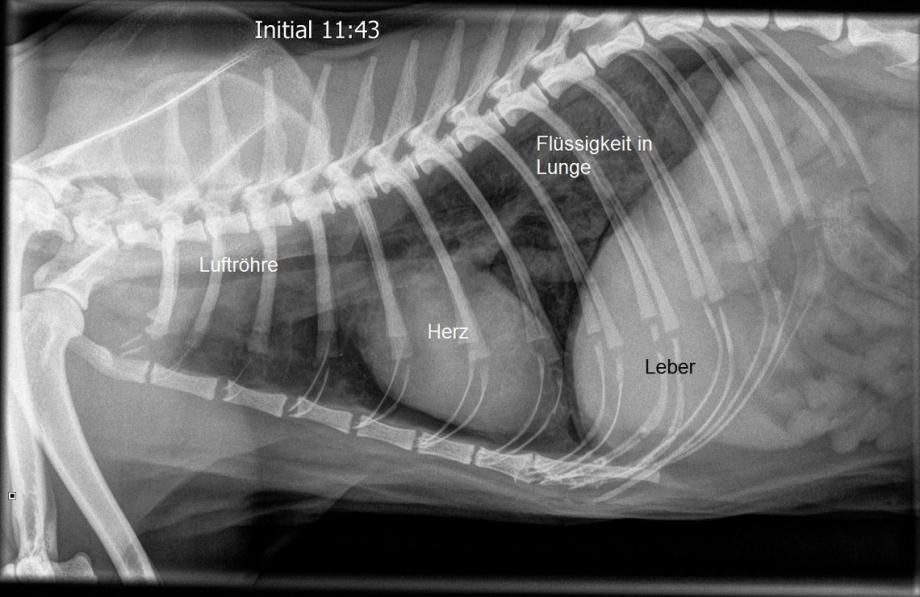

Sofort wird ein Röntgen des Brustkorbs angefertigt - bestürzt müssen wir feststellen, dass sich in den hinteren oberen Lungenarealen von Muffin ein Lungeninfiltrat (Flüssigkeit) gebildet hat, was die Schweratmigkeit erklärt.

Für diese Veränderung kommt vorerst insbesondere eine allergische Reaktion auf das verwendete Narkosemittel in Frage, bei dem durch die überschiessende Immunantwort ein Lungenödem gebildet wird. Muffin erhält sofort eine intravenöse Infusion zur Kreislaufstützung, ein hochdosiertes Cortison zur Blockierung einer allergischen Reaktion, ein Mittel zur Entwässerung sowie ein Gegenmittel zum verwendeten Narkosemittel. Ausserdem wird der Kater in eine Sauerstoffbox verbracht, um die Atmung zu verbessern.